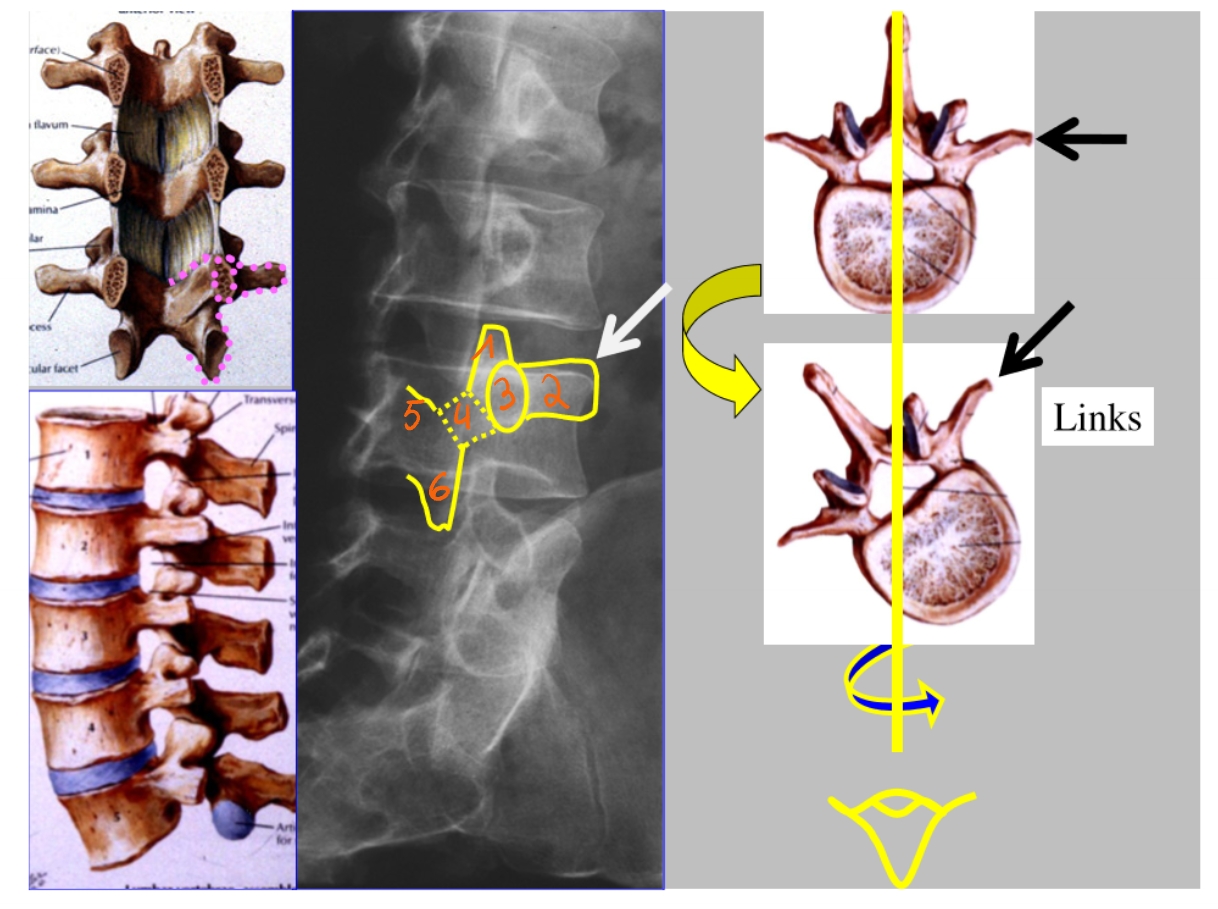

linker driekwart/ schuine opname

processus articularis superior

processus transversus

pedikel

isthmus = pars interarticularis

lamina

processus articularis inferior

CT-scan → dwarse doorsnede

durazak

ganglion spinale

ligamentum flavum

elastisch ligament, nodig om te buigen

flavum = geel

corpus

pedikel

canalis vertebralis

daarin: cauda equina + ruggenmerg → omgeven door durazak

lamina

arcus

processus transversus

embryologische rest van een rib

processus spinosus

nucleus pulposus

annulus fibrosus

psoas

facetgewricht